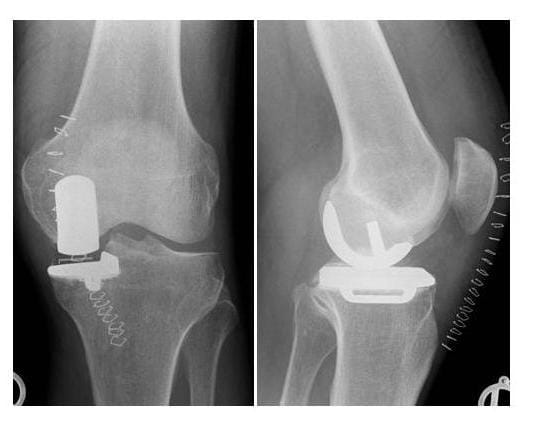

Röntgenbild Unikondylaerer Oberflächenersatz

Ersatz des verschlissenen inneren Gelenkanteiles mit einem Hemischlitten (Bilder: Orthopädie)